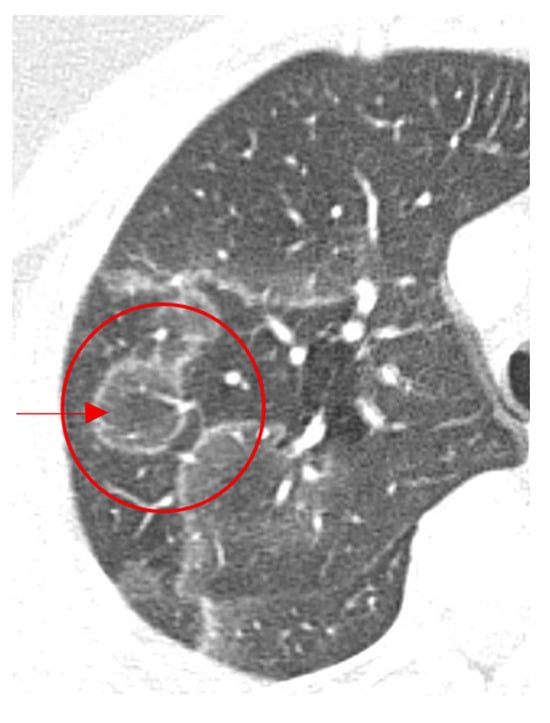

Chest